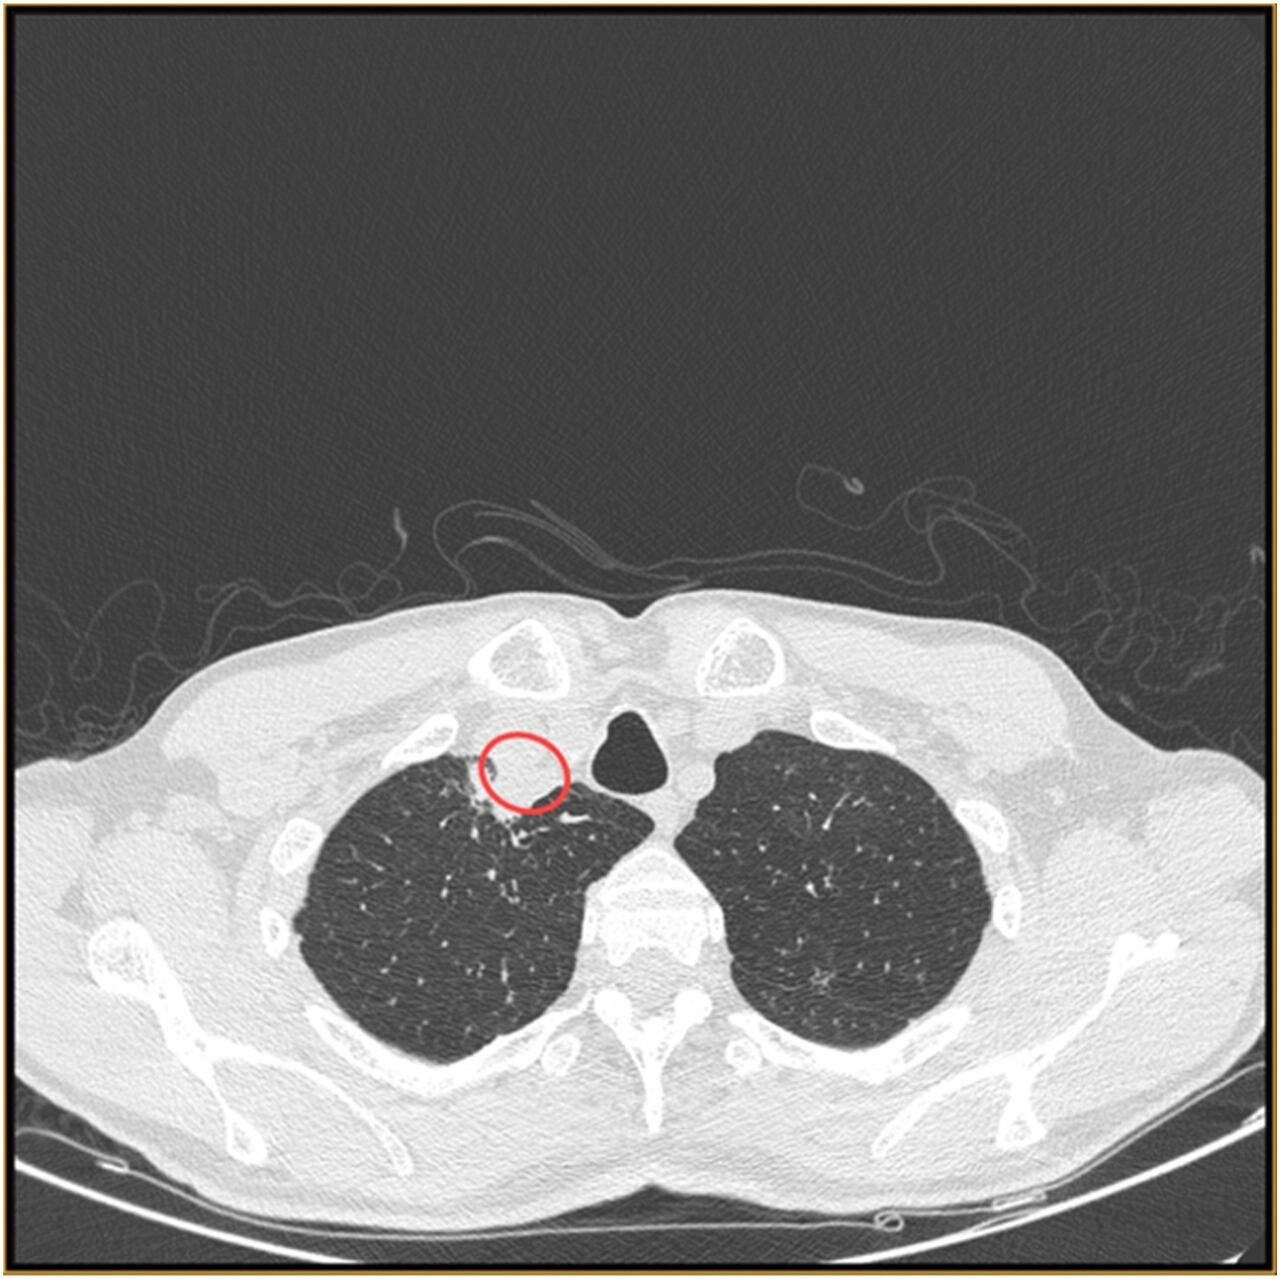

También el portal Science Direct compartió que en el estudio Absceso paratraqueal por hongo vegetal Chondrostereum purpureum, primer reporte de caso de infección humana, a través de una tomografía computarizada del cuello, se demostró la presencia de un paraabsceso traqueal.